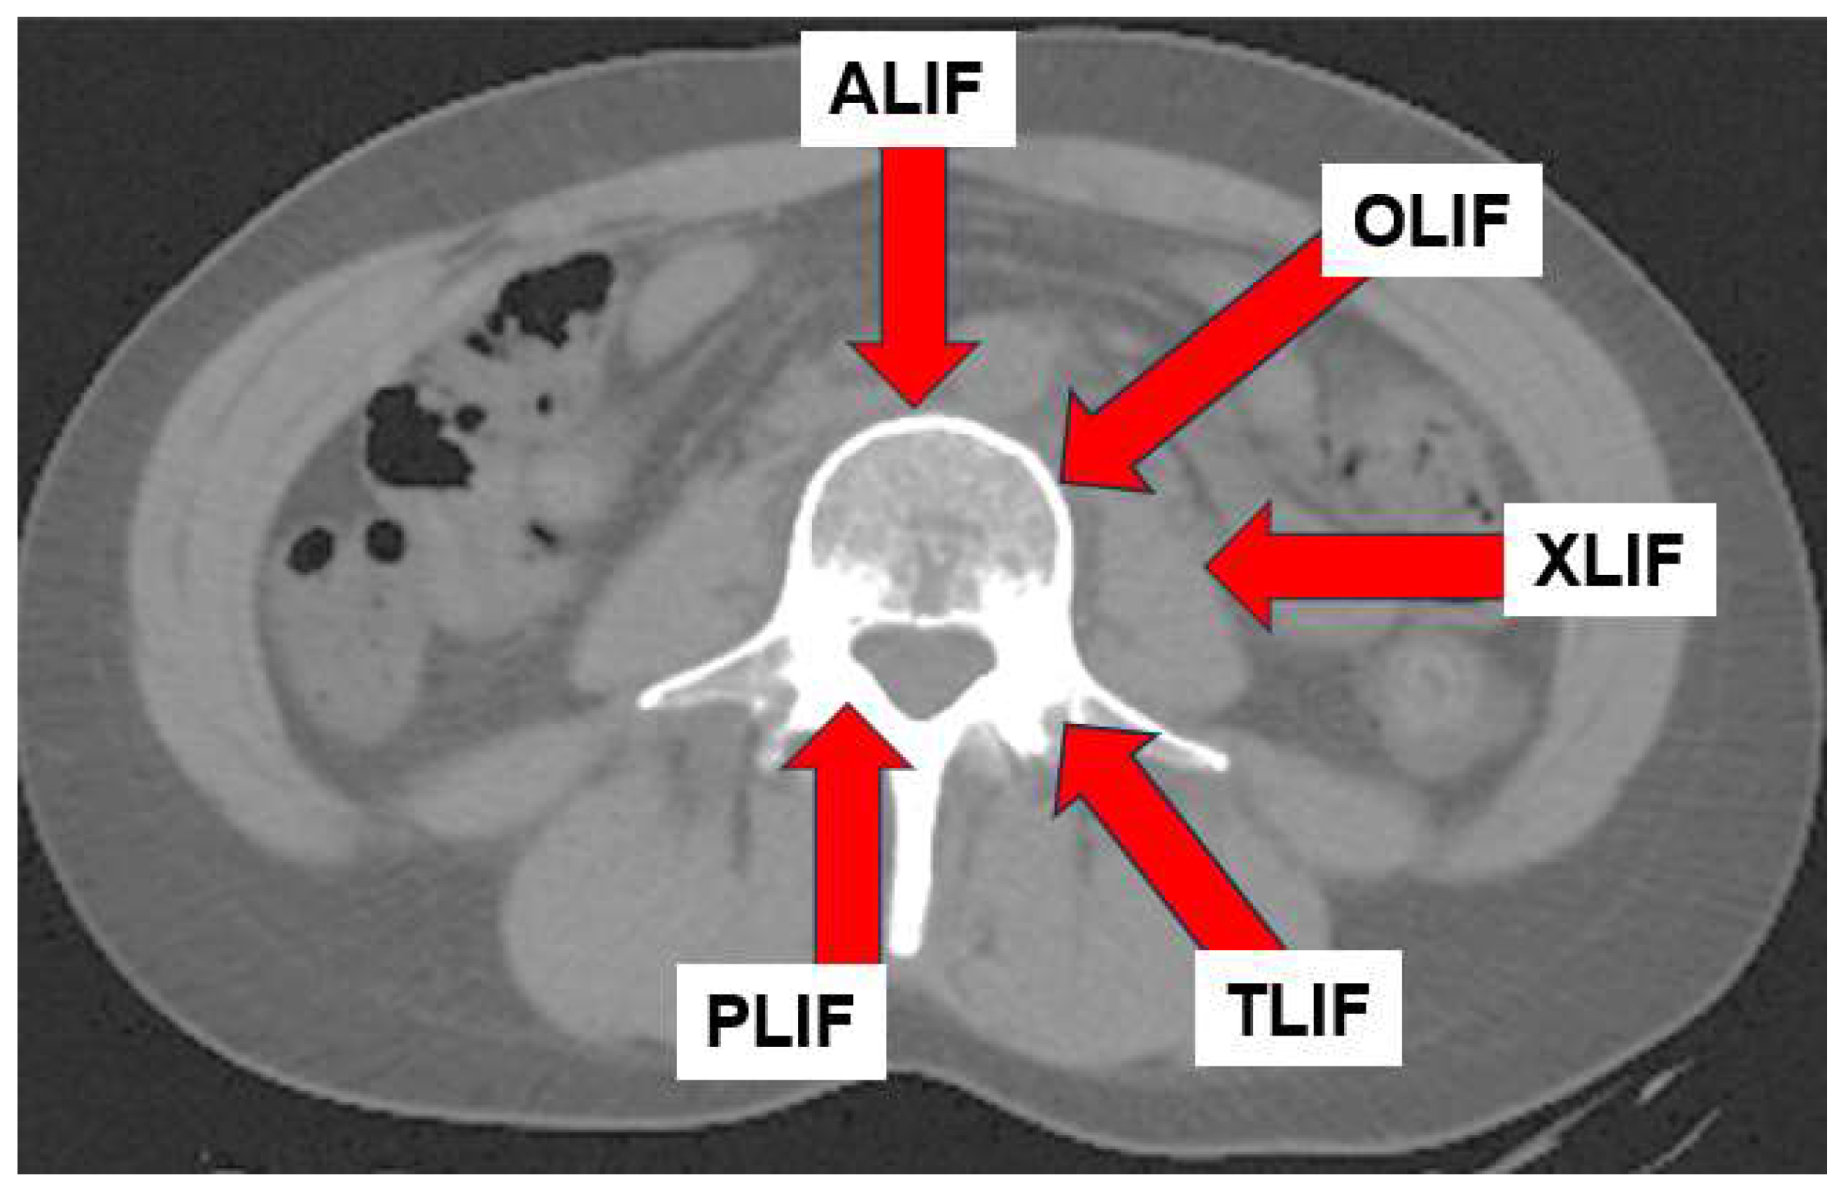

- Mobbs RJ, Phan K, Malham G, Seex K, Rao PJ. Lumbar interbody fusion: techniques, indications and comparison of interbody fusion options including PLIF, TLIF, MI-TLIF, OLIF/ATP, LLIF and ALIF. J Spine Surg. 2015 Dec;1(1):2-18. [CrossRef] [PubMed] [PubMed Central]